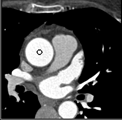

Samples for ascending aorta detection (black circle):

Cluster of candidate points in the ascending aorta.